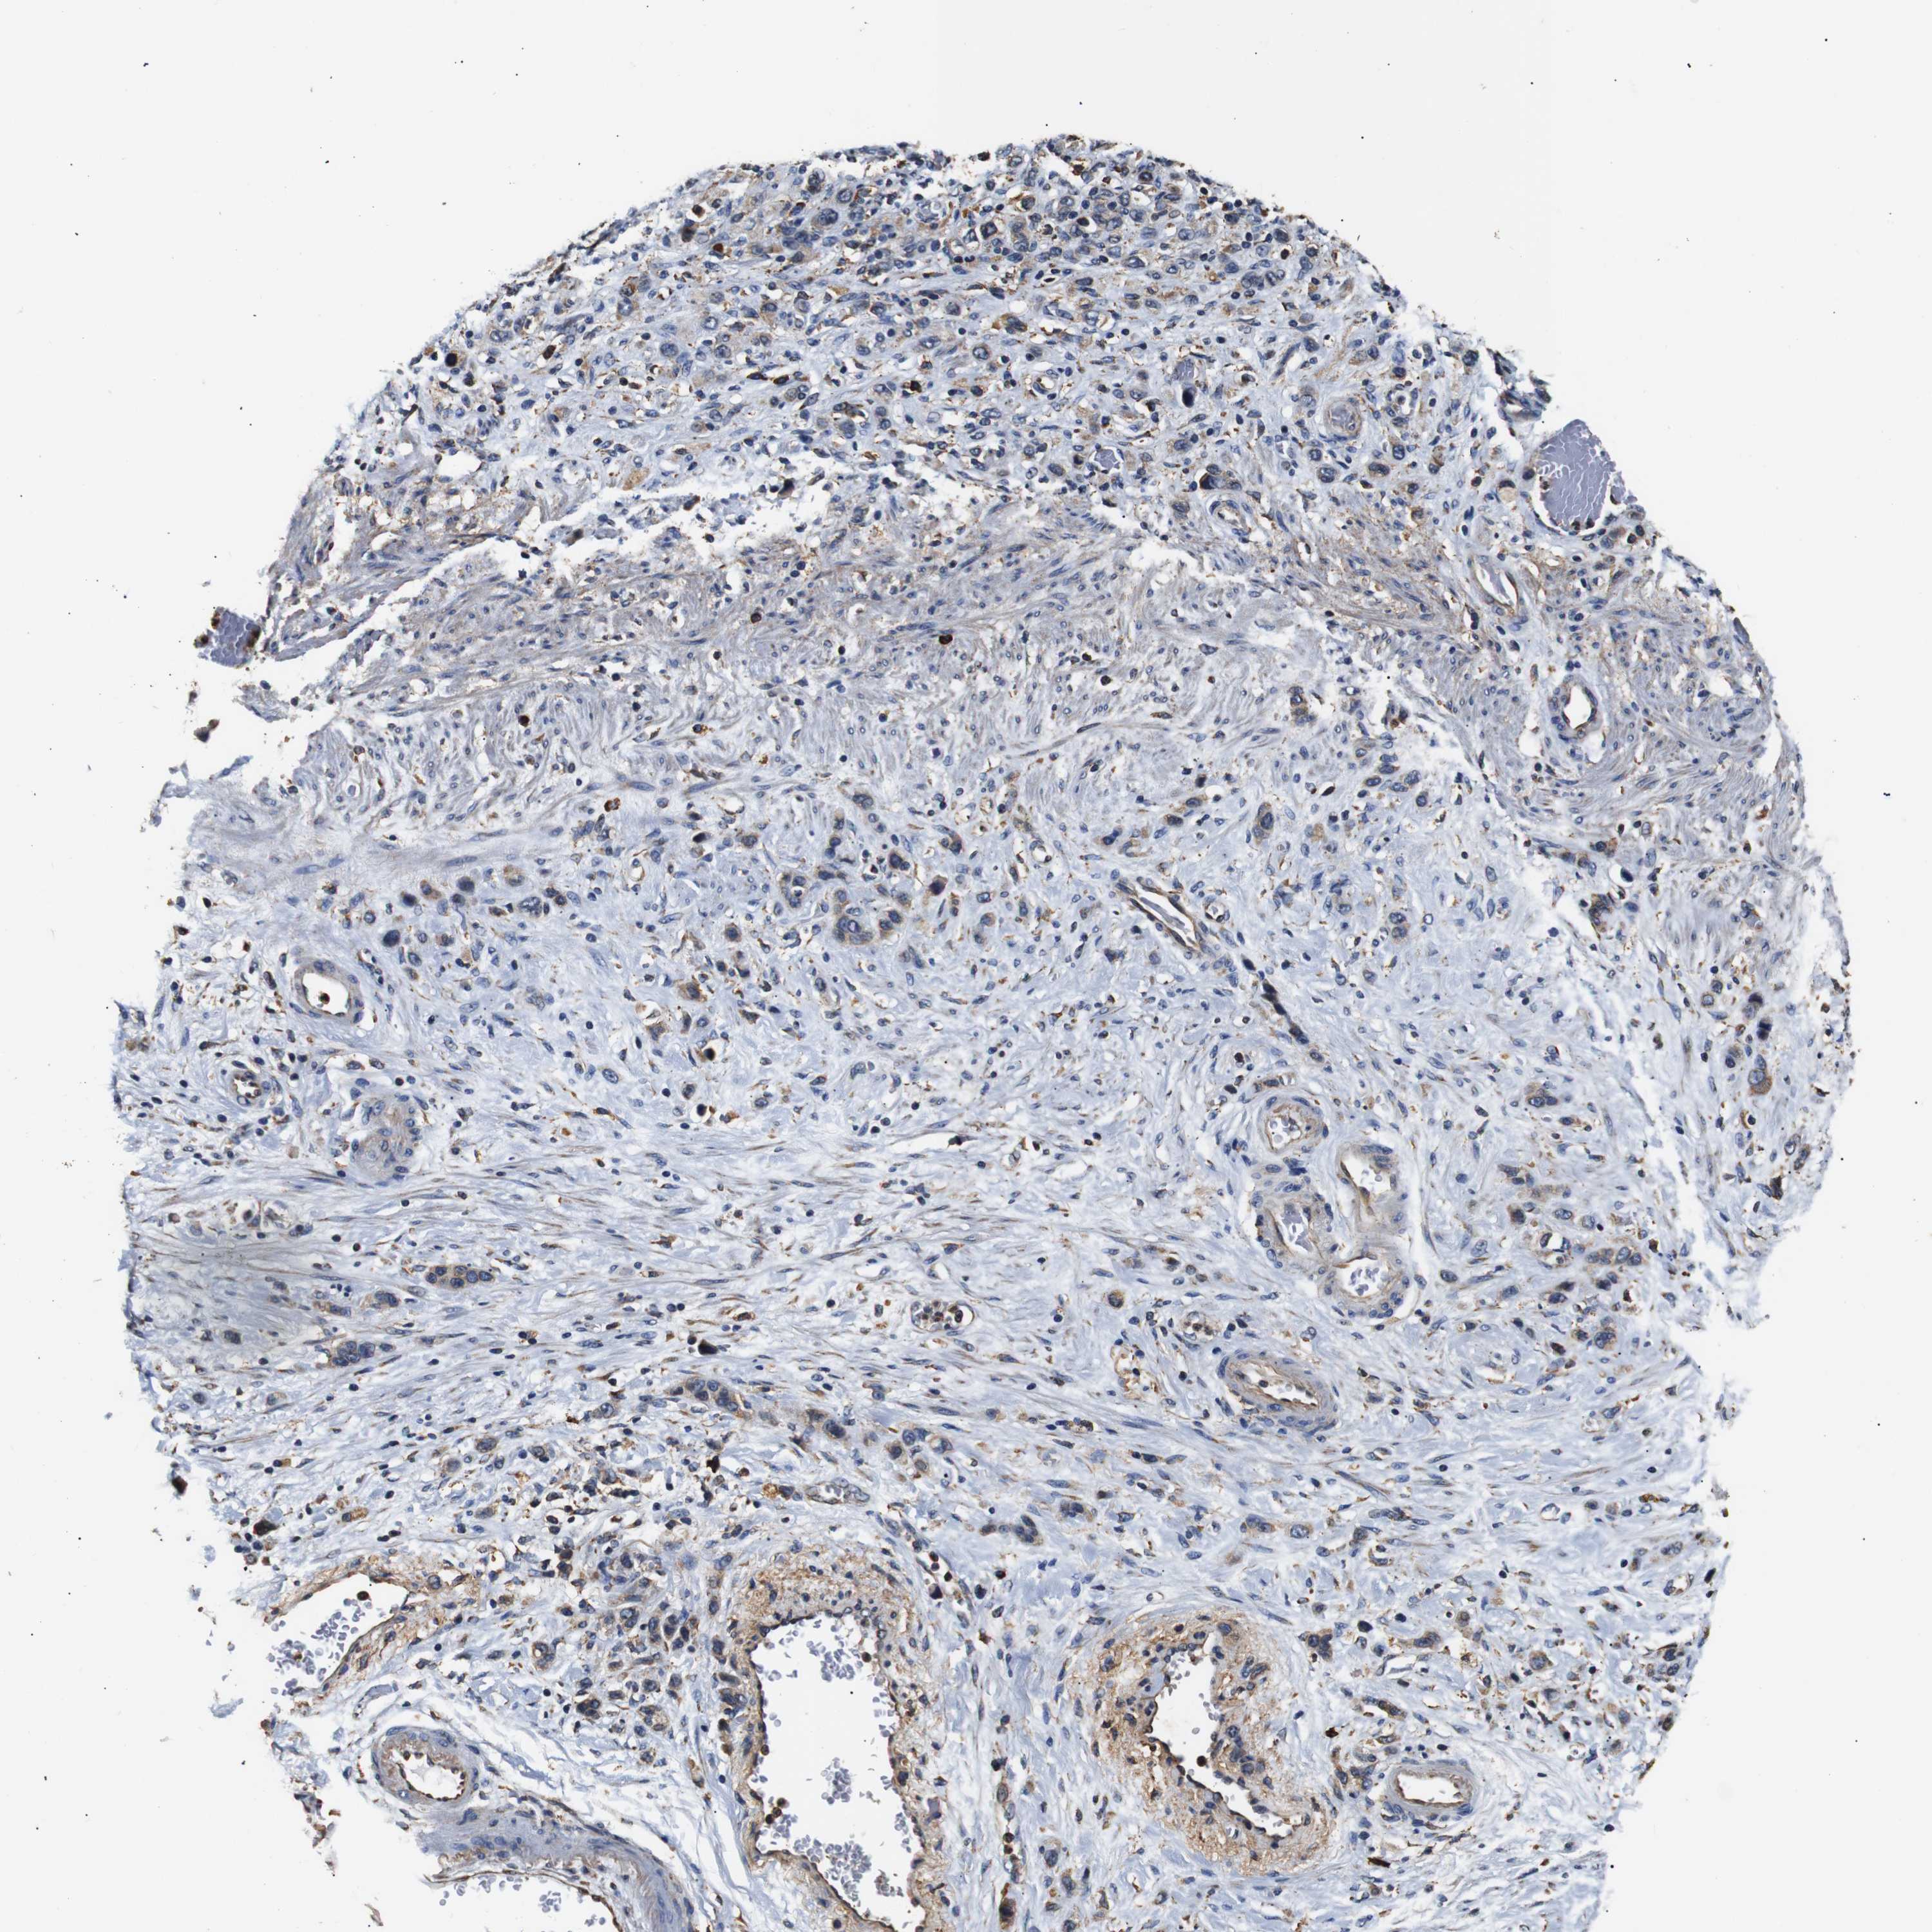

STOMACH CANCER - Protein expressioni

A mouse-over function shows sample information and annotation data. Click on an image to view it in a full screen mode. Samples can be filtered based on level of antibody staining by selecting one or several of the following categories: high, medium, low and not detected. The assay and annotation is described here.

Note that samples used for immunohistochemistry by the Human Protein Atlas do not correspond to samples in the TCGA dataset.

Antibody stainingi

Antibody staining in the annotated cell types in the current human tissue is reported as not detected, low, medium, or high, based on conventional immunohistochemistry profiling in selected tissues. This score is based on the combination of the staining intensity and fraction of stained cells.

Each image is clickable and will lead to virtual microscopy that enables deeper exploration of all samples and also displays staining intensity scores, fraction scores and subcellular localization as well as patient and tissue information for each sample.

Antibody HPA012616

Staining

High

Medium

Low

Not detected

Intensity

Strong

Moderate

Weak

Negative

Quantity

>75%

75%-25%

<25%

None

Location

Nuclear

Cytoplasmic/membranous

Cytoplasmic/membranous,nuclear

Adenocarcinoma, NOS

Adenocarcinoma, High grade